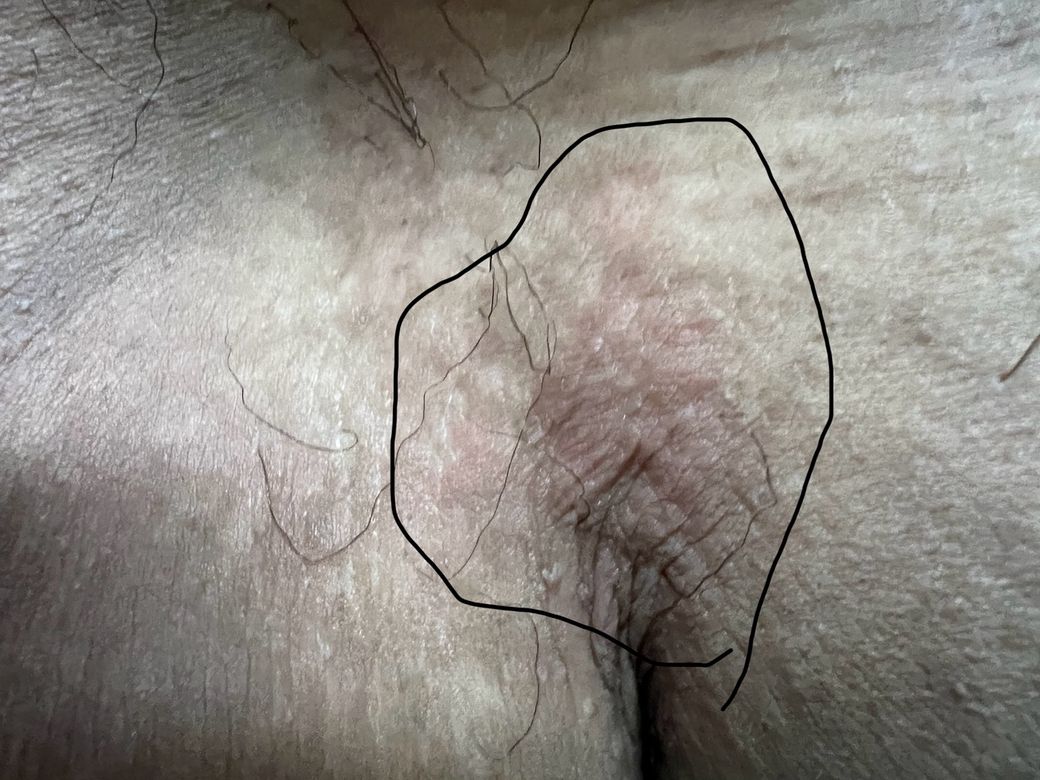

안녕하세요 사타구니가 시작되는 쪽부터 사타구니 살짝 위쩍에 이렇게 붉게 발진이 일어났습니다 이거 왜이러는지 혹시 알 수 있을까요? 혹시 성병(헤르페스 곤지름) 같은 전조증상일까요 답변해주시면 정말감사하겠습니다 ㅜㅜ

• 1번 째 사진

• 사진에서 보이는 병변은 사타구니 주름을 따라 퍼진 붉은 홍반과 약한 각질, 피부가 약간 두꺼워진 형태로 보이며, 물집이나 궤양, 사마귀처럼 돌출된 병변은 관찰되지 않습니다. 이러한 형태는 헤르페스나 곤지름의 전형적인 양상과는 차이가 있어 성병 가능성은 낮게 판단됩니다.

해당 부위 특성상 습기와 마찰이 많기 때문에 가장 흔한 원인은 완선(사타구니 진균 감염)이나 단순 마찰성·접촉성 피부염입니다. 특히 진균 감염은 가려움과 함께 경계 부위에 각질이 동반되며 땀, 운동, 꽉 끼는 속옷 등으로 악화되는 경향이 있습니다.

관리로는 부위를 건조하게 유지하고 통풍이 잘되도록 하며, 샤워 후 완전히 말리는 것이 중요합니다. 증상이 지속되면 항진균 연고를 하루 1회에서 2회, 2주에서 3주 정도 사용하는 것이 일반적이며, 스테로이드 연고 단독 사용은 피하는 것이 안전합니다.

1주에서 2주 내 호전이 없거나 병변이 넓어지거나, 통증성 물집이나 사마귀처럼 돌출되는 변화가 생기면 피부과 진료를 권장드립니다.